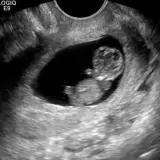

Ultrasound

75 cases Covering OB/GYN, GI/GU, and more